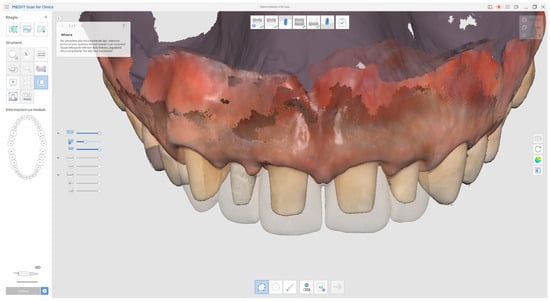

Due to restrictions related to the COVID-19 health emergency, the final impression phase was delayed and performed nine months later once soft tissue maturation had stabilised. Conventional impressions were obtained using the double-cord retraction technique (Figure 13 and Figure 14), followed by digital acquisition with the Medit i500 intraoral scanner (MEDIT Corp., MEDIT Corp, Seoul, Republic of Korea, Figure 14).

Figure 13. Nine-month follow-up.

Figure 14. Final digital impressions taken with Medit Scanner (i500) using double retraction cord technique.

In addition, the provisional restorations were digitised, and mandibular movements, along with maxillary spatial orientation, were recorded using the Zebris Jaw Movement Analysis System (zebris Medical GmbH, 88316 Isny, Germany, Figure 15).

Figure 15. Superimposed digital scans of the preparations and provisional restorations (transparent area) for prosthetic assessment.